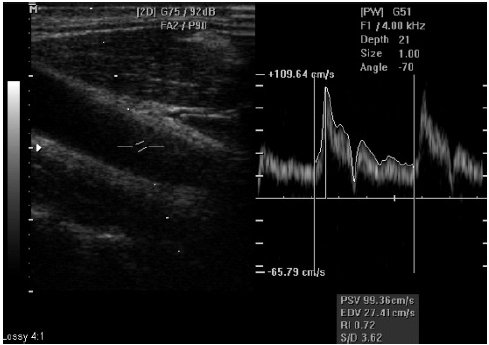

Avalie a imagem abaixo e marque a opção correta.

Corresponde a Doppler espectral com valores do pico de velocidade sistólica adequado para o sistema arterial do membro inferior

Para melhor análise deve-se apresentar também o Doppler colorido

O valor do pico de velocidade sistólica não deve ser considerado nesta avaliação

Há fenômenos de reflexão e a imagem deve ser refeita

Não há subsídios para a resposta porque o sistema vascular avaliado não foi informado